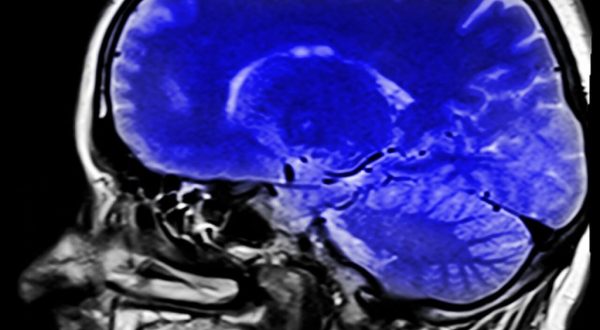

Esistono, però, alcune prove neurologiche che aiutano la diagnosi. La risonanza magnetica può mostrare il tipo di lesione cerebrale grazie alla quale è possibile orientarsi o meno verso questa sindrome.

Sia la tomografia a emissione di positroni (PET) sia l’elettroencefalogramma (EEG) possono dare informazioni sull’attività cerebrale. Tramite la PET si può osservare se il metabolismo cerebrale è normale, e in tal caso, significherebbe che le funzioni cerebrali si sono conservate e ci si preserva coscienti, come nella citata sindrome.